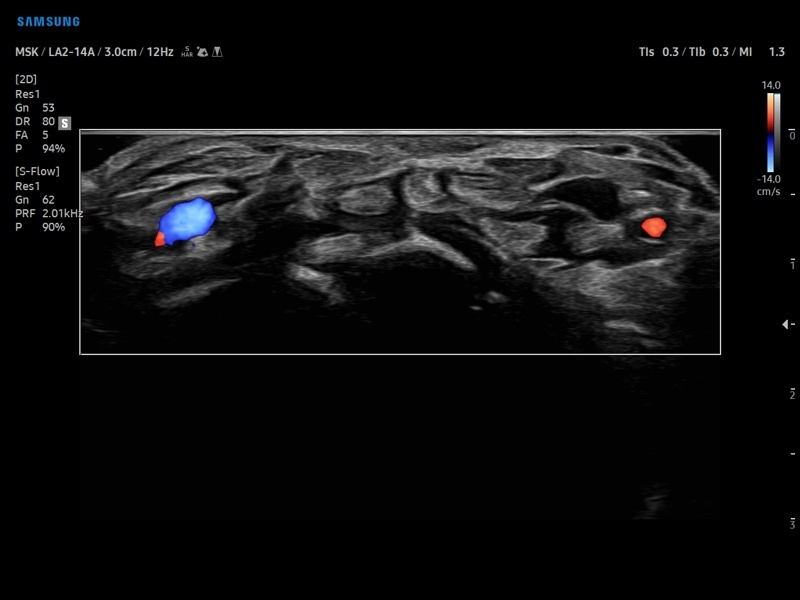

• Модуль NerveTrack – автоматическое определение срединного нерва в поперечном сечении с использованием искуственного интеллекта.

• Расширенная сосудистая визуализация: Auto IMT+, 2D Arterial Analysis